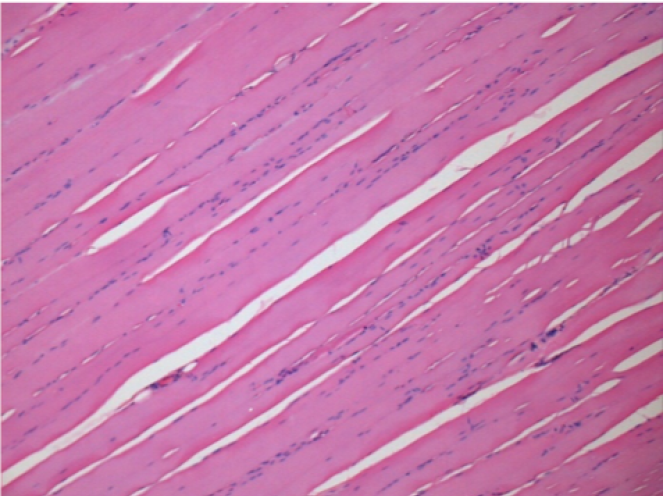

Через 3 місяці (90 днів) після ін'єкції Ендопіл 0,1 мл в правий претибіальний м'яз.

7 місяців (210 днів) після ін'єкції 0,1 мл Ендопіл в правий претибіальний м'яз.

Повна Restitutio ad integrum через 7 місяців